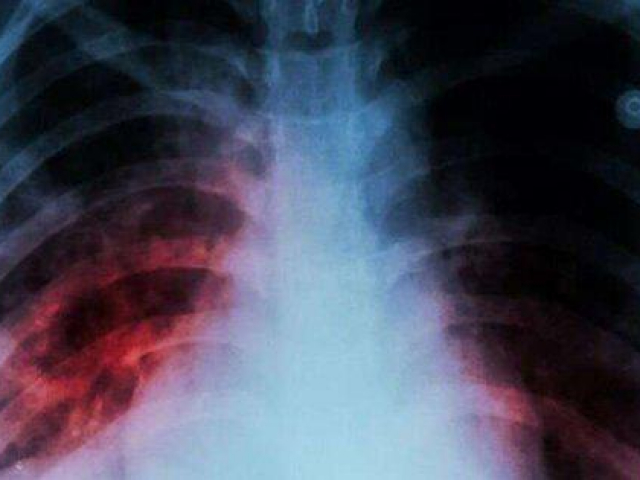

Tại sao ung thư ở người trẻ khó điều trị hơn ở người lớn tuổi?

Theo khảo sát và nghiên cứu hiện nay, tỷ lệ sống sót của thanh thiếu niên và trẻ em bị ung thư thấp hơn so với người già.

Từ những yếu tố trên cho thấy, bệnh ung thư ở người trẻ thường nghiêm trọng hơn người già, phát triển nhanh hơn, mức độ ác tính nặng hơn, tỷ lệ tử vong cao hơn.

Với tình trạng ung thư đang dần trẻ hóa, người trẻ tuổi nên tăng cường phòng chống ung thư, không chủ quan khi có những dấu hiệu bất thường.